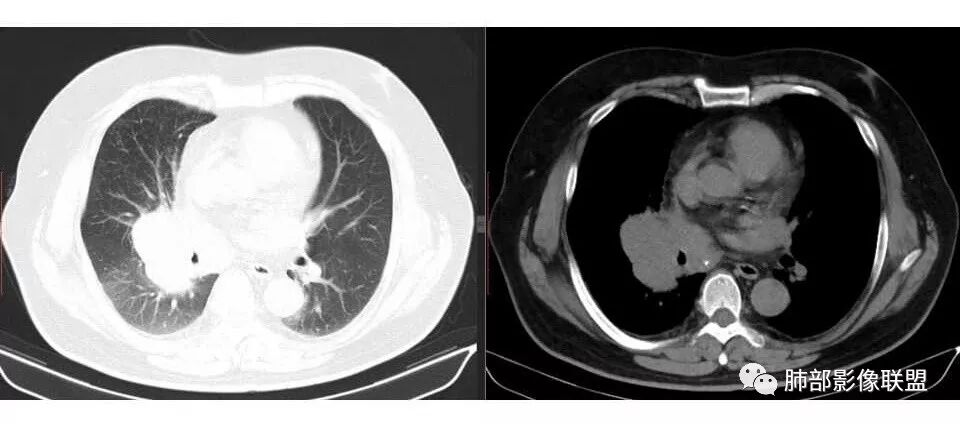

张帅: 患者以肢体无力就诊,既往有吸烟史,胸CT:右肺门占位性病变,密度不均,病灶内病灶内支气管明显狭窄,走行僵硬,病灶边缘光滑,呈浅分叶,未见明显毛刺,对中叶支气管明显挤压。右肺内可见散在片状实变影,前纵隔淋巴结明显肿大,内可见低密度区,2r 4r 7 10r淋巴结明显肿大。诊断考虑恶性方向,肺癌(小细胞)并纵隔肺门淋巴结转移?淋巴瘤?

wonderful: 右肺门巨大占位,支气管均受压变窄,但支气管内无肿瘤,首先考虑小细胞癌

支气管狭窄,壁有侵犯

局限性中央间质增厚,考虑癌性淋巴管炎

这么大,肺门区,如果纵隔型肺癌,按理是中央型,常规——支气管为主

这一例表现反了,支气管稍受侵犯

南边: 而且肺癌,一定受叶段的局限,这一例跨越右肺门,提示多个淋巴结融合

南边: 例如这个病灶,如果是一个孤立的肿块,边界清晰,提示破坏性不强,不应该是包绕支气管,是推移到一边为主,这个表现为包绕,提示是多个病灶融合

1.右肺上叶不规则结节影,右肺门及纵隔多结节并形成巨大块影,密度均匀,沿途支气管明显狭窄。

原发灶小或隐匿,肺门纵隔淋巴结异常增大,所谓“娘小崽大”常见于肺小细胞癌!